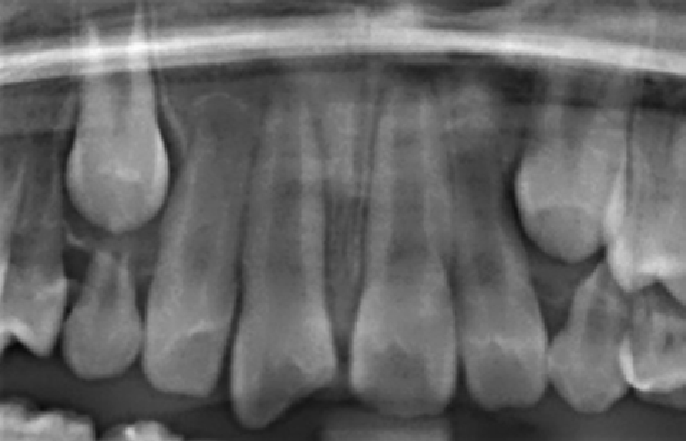

immature apex open apexogenesis young tooth radiograph

Cas Clinique 3 : Exposition Pulpaire et Dentinogenèse Réparatrice

Patient : Garçon de 11 ans. Traumatisme dentaire au cours d’une activité sportive. Fracture coronaire complexe sur la 21 (incisive centrale maxillaire gauche) avec exposition pulpaire confirmée.

Présentation clinique : Saignement punctiforme au niveau de la pulpe exposée. Test de vitalité positif. Apex non encore fermé (apex ouvert : apex immature). Pas de signe de nécrose.

Problématique : Sur une dent à apex immature avec pulpe vitale, l’objectif prioritaire est de maintenir la vitalité pulpaire pour permettre la complétion radiculaire (apexogenèse). Le recours immédiat à un traitement endodontique compromettra cette évolution.

Prise en charge : Coiffage pulpaire direct au MTA (Mineral Trioxide Aggregate) sous champ opératoire rigoureux (digue). Restauration provisoire étanche. Contrôles cliniques et radiographiques à 3, 6 et 12 mois.

Évolution attendue : Formation d’un pont dentinaire réparateur en 4 à 8 semaines, confirmé radiographiquement. Poursuite de l’apexogenèse. Ce cas illustre le concept de dentinogenèse réparatrice : les cellules progénitrices pulpaires recrutées reforment une barrière calcifiée qui protège la pulpe et permet la poursuite du développement radiculaire.